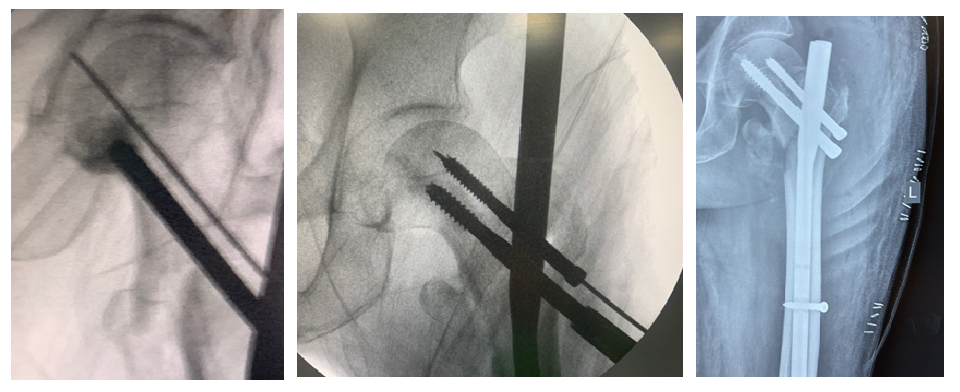

Fig. 4: Cement inserter device

Fig. 5: Bone cement

After obtaining necessary measurements, poly methyl methacrylate (PMMA) (fig. 5) bone cement was prepared, and using newly designed device, the cement was inserted (in doughy state) into the femoral head through predrilled screw site under fluoroscopic supervision (fig. 6).

Fig. 6: Cement inserted

Fig. 7: Screw inserted